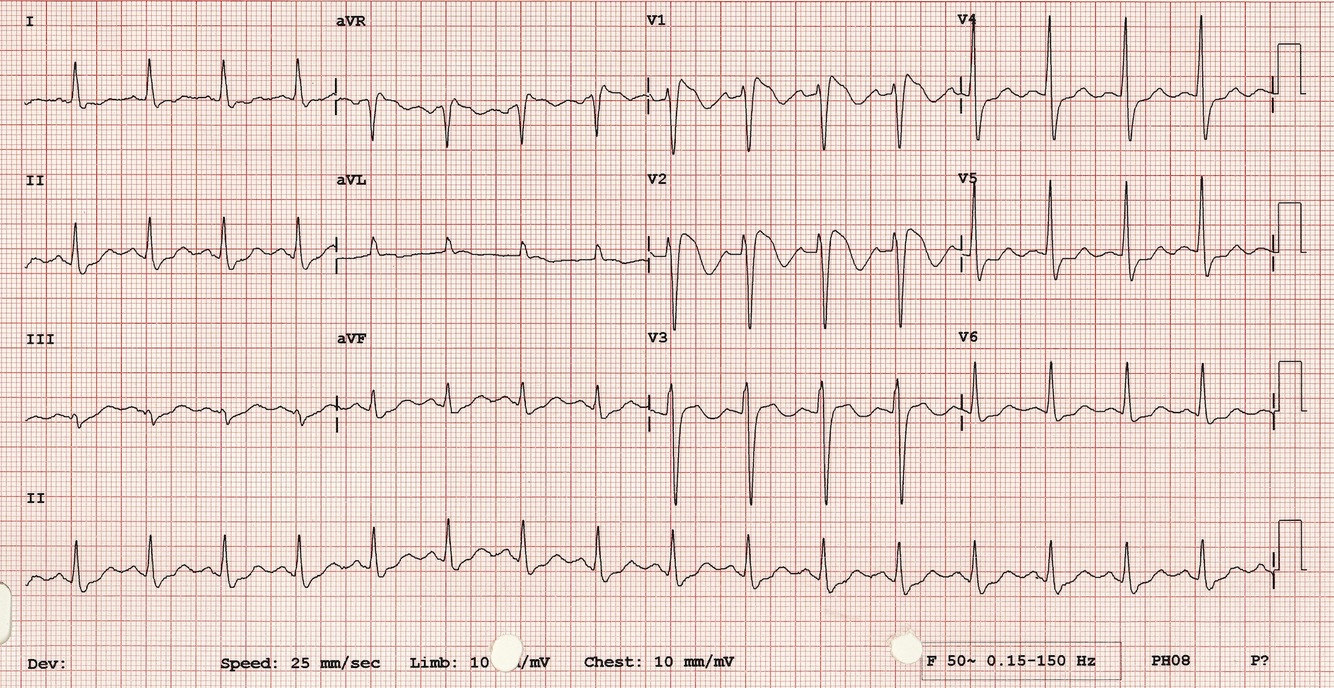

Right Bundle Branch Block

Features rSR in Lead V1-V3 (M)

Lateral leads I, AVL, V5-V6 have a slight slur to the S wave (W) qRs

QRS if < 120 incomplete (esp young children, usually inocent),

QRS > 120 complete

Causes of Complete RBB include: PE, Right ventricular hypertorphy, IHD, Rheumatic HD, Myocarditis, Degenerative disease, Congenital Heart defect eg ASD.